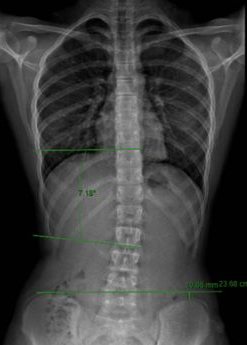

Όπως προτείνει η Scoliosis Research Society (SRS), η διάγνωση της σκολίωσης επιβεβαιώνεται όταν ένας ασθενής παρουσιάζει γωνία Cobb 10° ή μεγαλύτερη και αξονική στροφή του σπονδύλου. Το SRS καθόρισε αυτό το όριο το 1977, αντικαθιστώντας το προηγούμενο των 7°.

Έκτοτε, το 10° έχει γίνει συμβατικά αποδεκτό, παγκοσμίως, ως το κατώφλι για τη διάγνωση της σκολίωσης.

Ωστόσο, η δομική σκολίωση, με δυνατότητα εξέλιξης, μπορεί επίσης να παρατηρηθεί παρουσία γωνιών Cobb μικρότερες από 10°.

Στην πραγματικότητα, η σφηνοειδής παραμόρφωση των σπονδυλικών σωμάτων και δίσκων μπορεί μερικές φορές να καταγραφεί με γωνίες 4°–7°.